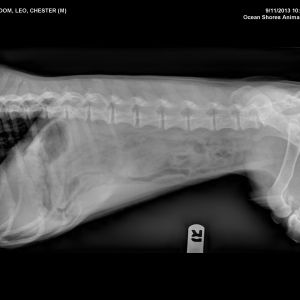

He enjoyed our beach RV trips in particular. Perhaps a little too much, though? The x-ray in the slide show below was a souvenir of a beach trip where we discovered Chester’s love of crab — particularly crab shells (we believe) — and the negative impact they had on his guts.

I had forgotten that Chester was the one who ate the crab shells! That was so scary and such a cautionary tale to me. I always tell friends about that when at the beach and their dogs are running and sniffing at all the debris washed up. No crab shells! Love the photos and it was so lucky you snapped that one when he was a puppy. Thinking of you both.